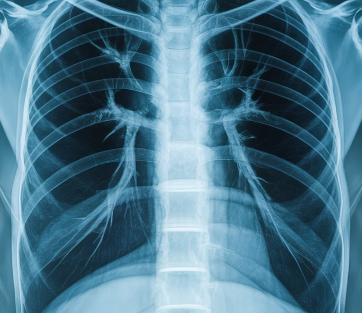

Q3. 폐암 초기에도 X-ray로 발견되나요?

초기는 X-ray에서 보이지 않을 수 있어

저선량 CT 검사가 훨씬 정확합니다.